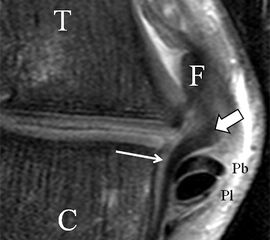

Der Ursprung des Ligamentum fibulocalcaneare liegt unmittelbar kaudal und dorsal des Ursprungs des Ligamentum fibulotalare anterius, so dass gehäuft kombinierte Verletzungen und auch ein gemeinsamer knöcherner Ausriss beobachtet werden. Nach kaudal dorsal verläuft das Band dann nach medial konvex unter die Peroneussehnen. Danach ist ein schräg deszendierender, gestreckter Verlauf bis zum calcanearen Ansatz abgrenzbar (Abb. 10). Dieser zu allen drei Standardebenen schräge Verlauf erschwert häufig die Diagnostik des LFC vor allem bei subtileren Verletzungen. Spezialprojektionen, die dem Bandverlauf orthograd folgen (entweder schräg coronar oder schräg sagittal) erleichtern auch hier die Diagnostik (Abb. 11) insbesondere nicht dislozierter Avulsionen. Assoziierte Verletzungen der Peroneussehnenloge müssen mit beurteilt werden, wobei neben Verletzungen der Sehnen und Sehnenscheiden die Beurteilung des Retinaculum peroneum superius und inferius wichtig ist. In einem Kollektiv von Patienten mit chronischen Außenbandinstabilitäten weisen 50% der Patienten eine Verletzung dieser Strukturen auf 5. Auch hier erleichtern hochauflösende Techniken die Diagnostik (Abb. 12).